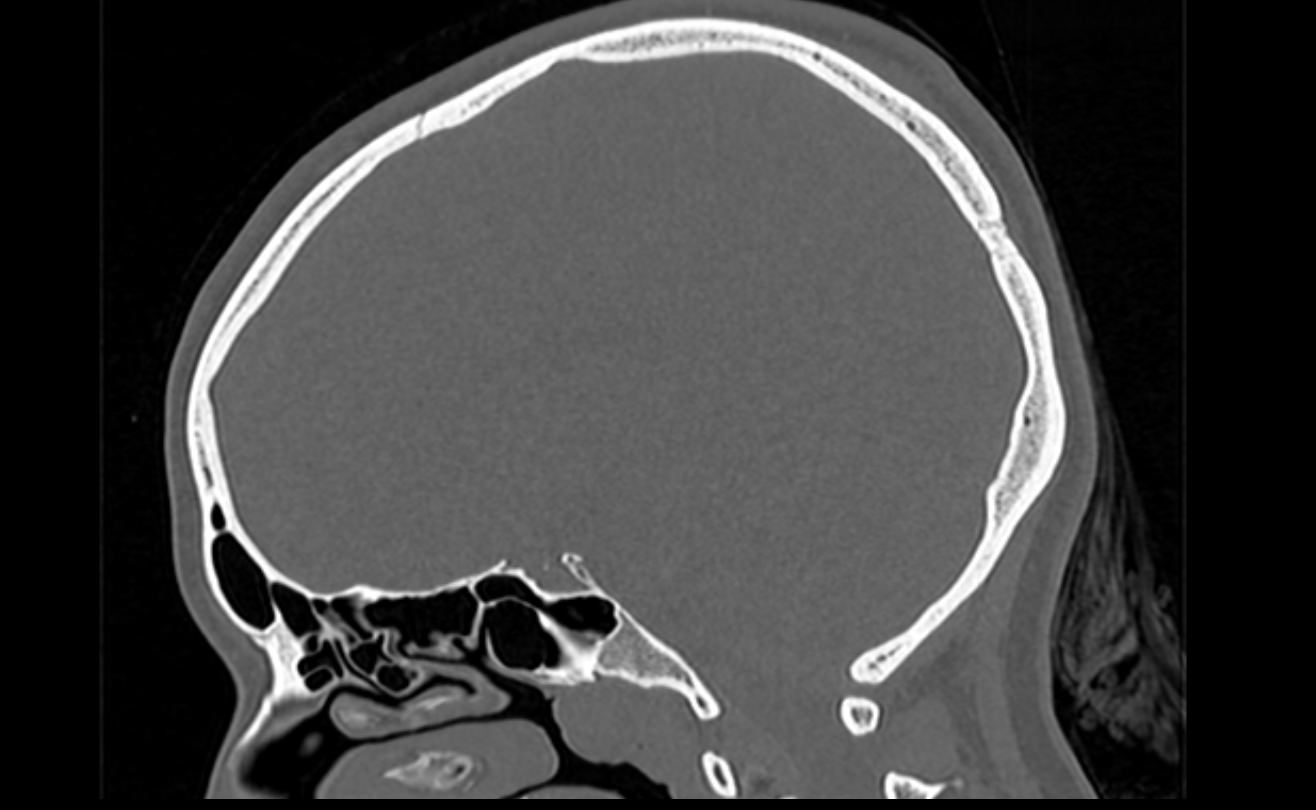

Мультиспиральная компьютерная томография является наилучшим методом диагностики патологии костей черепа. В основе методики лежит использование рентгеновского излучения с последующей цифровой обработкой полученных данных и получения трехмерных реконструкций изображений.

Костная ткань отличается высокой плотностью и способна в большой степени поглощать рентгеновские лучи. Поэтому на послойных снимках, полученных при проведении мультиспиральной КТ черепа можно детально рассмотреть свод черепа, кости лица, основание черепа. Это позволяет с наибольшей точностью визуализировать различные объемные образования, такие как остеомы, дифференцировать фиброзную дисплазию или костные метастазы. Преимуществами методики КТ является отличная визуализация костных структур, быстрота выполнения процедуры и доступная цена. Все это делает КТ незаменимой при диагностике травматических повреждений (например переломов основания черепа или орбит), аномалий развития, при планировании оперативных вмешательств.